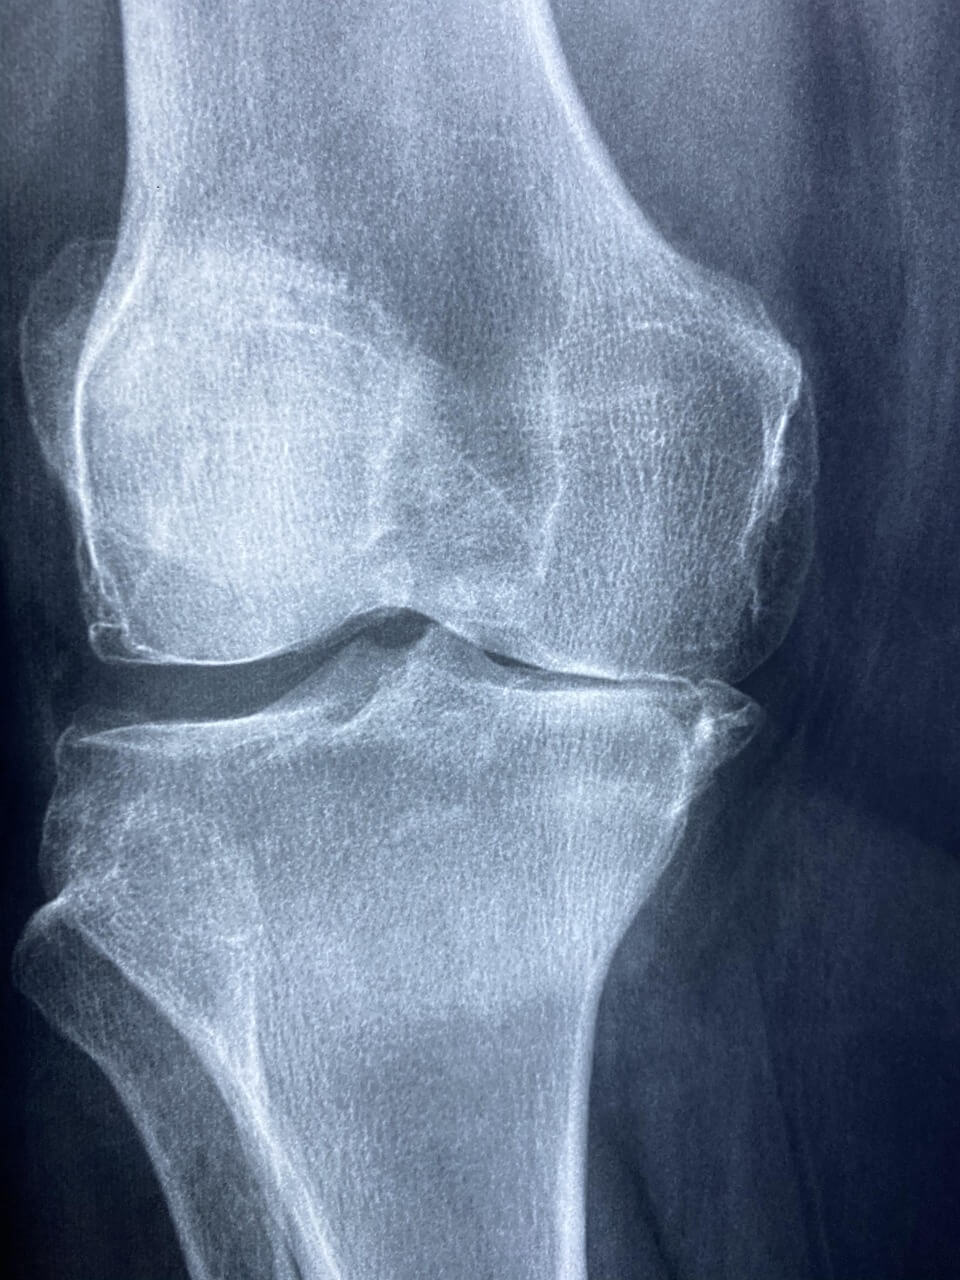

1. 무릎통증 원인, 퇴행성 관절염 (연골이 닳아 생기는 마찰 통증)

퇴행성 관절염은 무릎 관절 사이의 연골이 마모되면서 관절면이 서로 맞닿아 통증과 염증을 유발하는 질환입니다. 나이가 들면서 자연스럽게 발생하기도 하지만, 비만, 무리한 운동, 무릎 부상 등이 무릎통증 원인이 될 수 있습니다. 연골은 신경이 없어 아프지 않지만, 마모되면서 주변 뼈와 조직에 염증을 일으켜 무릎통증이 나타나는 것입니다.